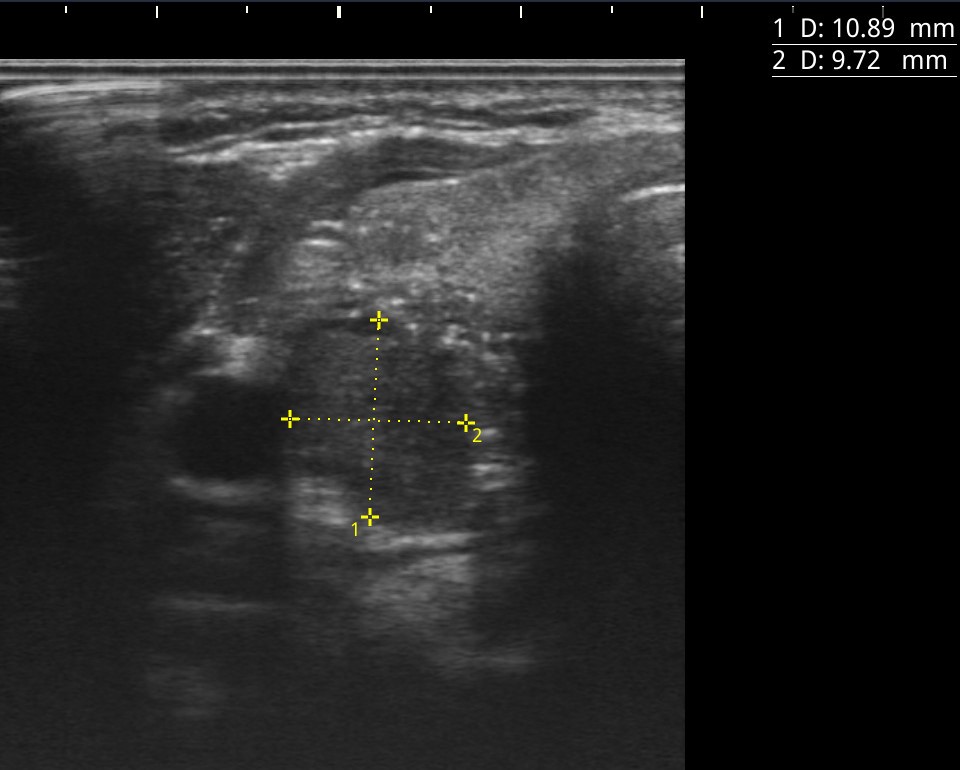

Hallazgos ecográficos

Nódulo de 16,9×15,1 mm, sólido, hipoecoico, de bordes mal definidos, más alto que ancho y con microfocos ecogénicos y calcificación periférica en anillo. Se clasifica como TIRADS 5, altamente sospechoso de malignidad e indicativo de PAAF al superar los 10 mm.